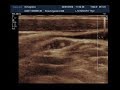

Первые Признаки РАКА ГРУДИ. Как выглядит рак молочной железы (фото на снимке УЗИ)